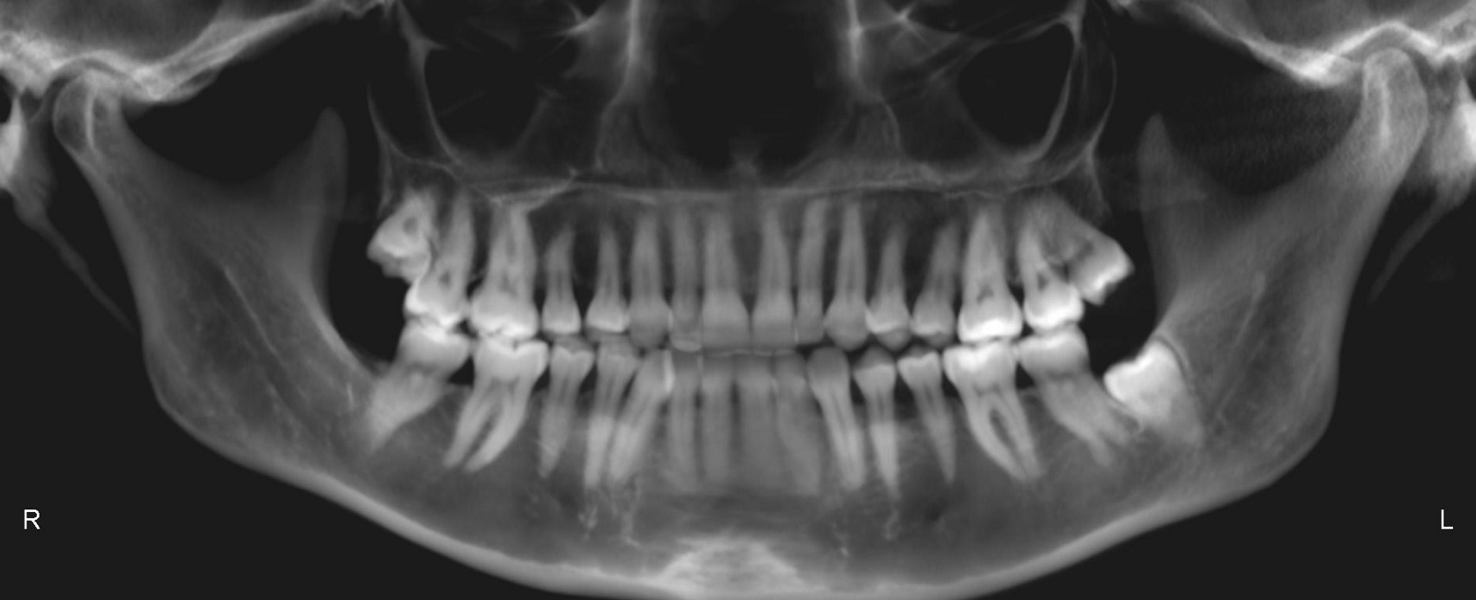

The final dental panoramic tomogram showed the correct levelling of the occlusal planes and root positions (Fig. 26). The final cephalometric tracing showed closure of the facial angle thanks to the posterior intrusion and mandibular auto-rotation (Figs. 27 & 28). Mandibular antero-rotation shortens the lower facial third, improving lip competence and ultimately the facial profile. The CBCT images of the TMJs showed the correct position of the condyles within the glenoid fossae (Fig. 29). When looking at the airway on the CBCT scan, we also saw an improvement of the patient’s airway (Fig. 30).

Fig. 26: Post-treatment dental panoramic tomogram.